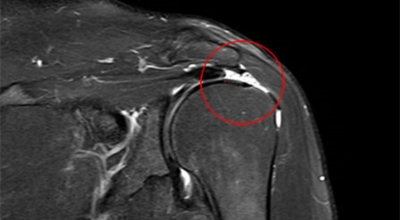

회전근개가 파열되는 경우 어깨에 통증이 생기게 되어요. 회전근개는 어깨 회전 운동에 영향을 줌으로써 팔을 들어올리는 동작에 제약이 생기기도 합니다. 이러한 증상은 오십견 증상과 비슷하기도 한데요. 수동적 움직임도 제한되는 오십견과는 달리 다른 사람의 도움을 받게 되면 팔을 들어올릴 수 있다는 차이가 있답니다.

회전근개파열은 가만히 서 있는 경우 통증이 줄어들기도 하지만 눕는 경우 통증이 더 심해지며 통증이 발생한 부분으로 돌아 눕기가 어려워 수면 장애를 동반할 수도 있죠. 그리고 어깨는 수시로 쓰이는 부위인 만큼 통증이 발생하다 보면 일상에도 큰 불편함을 줄 수 잇어 초기에 치료를 받는 것이 좋을겁니다. 다음 증상은 움직일 때 소리가 나는 증세입니다. 자주는 아니긴 하지만 어깨를 360도 돌릴 때 마찰음이 들리는 증상이 있습니다.

어깨를 포함한 팔의 움직임이 제한됩니다. 가장 동일한 증상이고 전반적인 움직임에 제한이 있어서 일상생활을 하는데 불편함을 호소하게 되어요. 다음 어깨 회전근개파열 증상으로는 관절염과 탈구입니다. 상완골두 즉 상완을 구성하는 뼈가 증가해 견봉과 맞닿으면서 뼈끼리 닿아서 관절염이 될 수 있답니다. 최악의 경우 파열이 왔는데 방치하면 탈구로 이어질 수 있기 때문에 조심해야겠습니다. 세팔을 위로 뻗기가 힘듭니다. 본인 스스로가 팔을 못 들어 올리는 상태가 되는데, 다른 사람이 올려주면 올릴 수 있지만 손을 떼어버리면 힘이 빠져서 팔을 떨구게 되어요. 어깨 바깥이나 앞쪽의 통증이 나타나게 돼요.